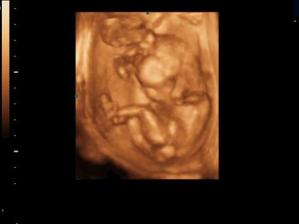

Naše kinderka

Dňa 24.8.2009 o 9.15 sa nám sekciou narodili naše krásne dvojičky Vanesska 2280 g a Larinka 2990 g. Robia nám veľkú radosť a moc ich ľúbime...